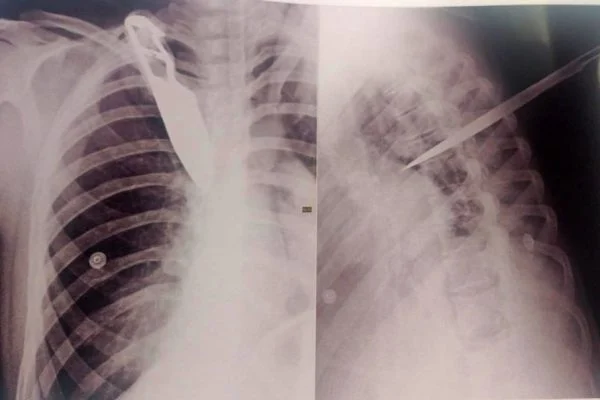

São Paulo – Uma mulher de 33 anos ficou com uma faca cravada nas costas após ser atacada pelo ex-companheiro durante uma discussão na terça-feira (28/12), em Garça, no interior de São Paulo. O agressor fugiu após o crime, mas acabou preso na cidade vizinha Gália.

Ela passou por cirurgia e segue internada na Unidade de Terapia Intensiva (UTI) do Hospital das Clínicas (HC) de Marília.